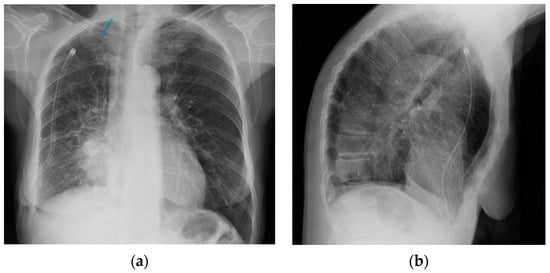

8.1. Cerebrospinal Fluid (CSF) Shunts

8.2. Vagal Nerve Stimulator (VNS)